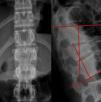

Marcadores de inestabilidadÍndice sagital de Farcy3Se mide en el plano sagital y determina el grado de acuñamiento en este plano. Es un ángulo constituido por 2 líneas que resultan de las proyecciones de los platillos inferiores de la vértebra craneal a la fracturada y de esta misma. Se considera inestable cuando el valor es superior a 16°, corregido en función del nivel de la fractura. La corrección se realiza restando 5° a la medición en el caso de fracturas a nivel torácico y sumando 10° a nivel lumbar; las fracturas localizadas en la charnela no precisan corrección (fig. 1).